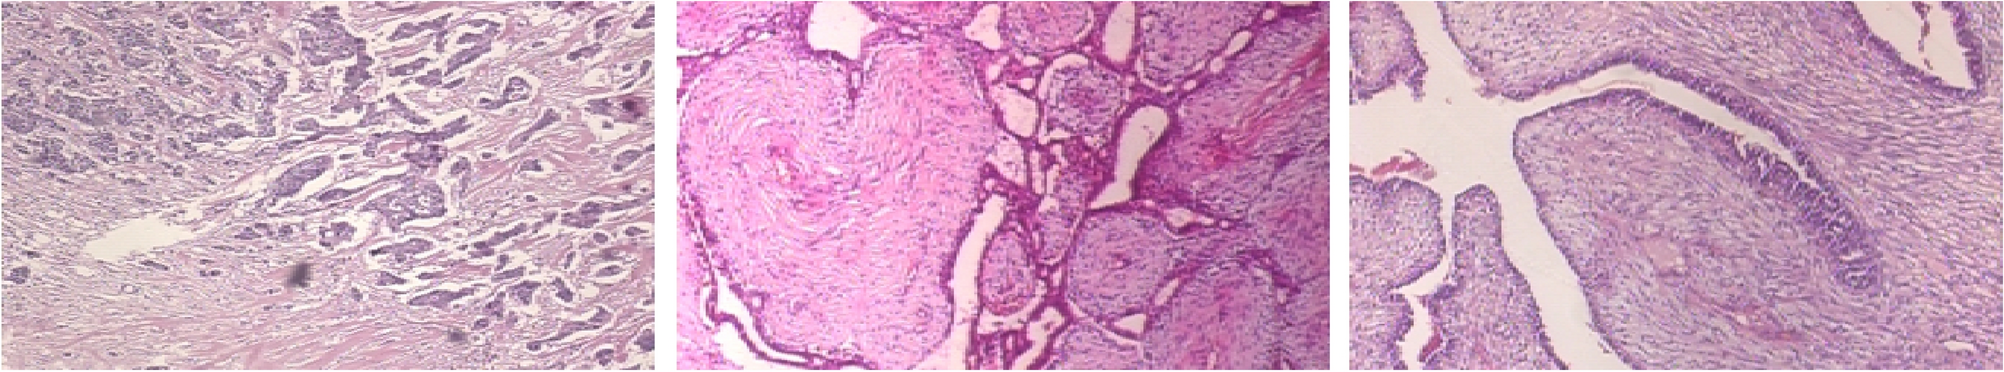

Sample images of the BreakHis-40\(\times \) dataset.